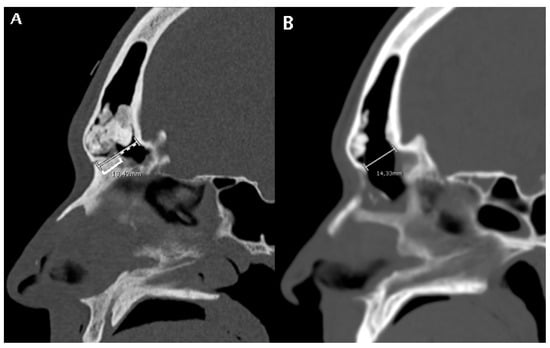

Figure 2.

A patient subjected to a DRAF III for relapse of osteoma and fronto-orbital mucocele. (A) shows a pre-operative CT scan where FOAP max (white line) is measured as the sum of the mid-sagittal thickness of the nasal beak (white square bracket) and the mid-sagittal distance between the nasal beak and the most anterior skull base (white dotted line). (B) shows the post-operative CT scan on the same mid-sagittal section. The white line represents the maximum anteroposterior diameter of the frontal sinus neostium after surgery, which we termed obtained diameter (OD, see Figure 5).